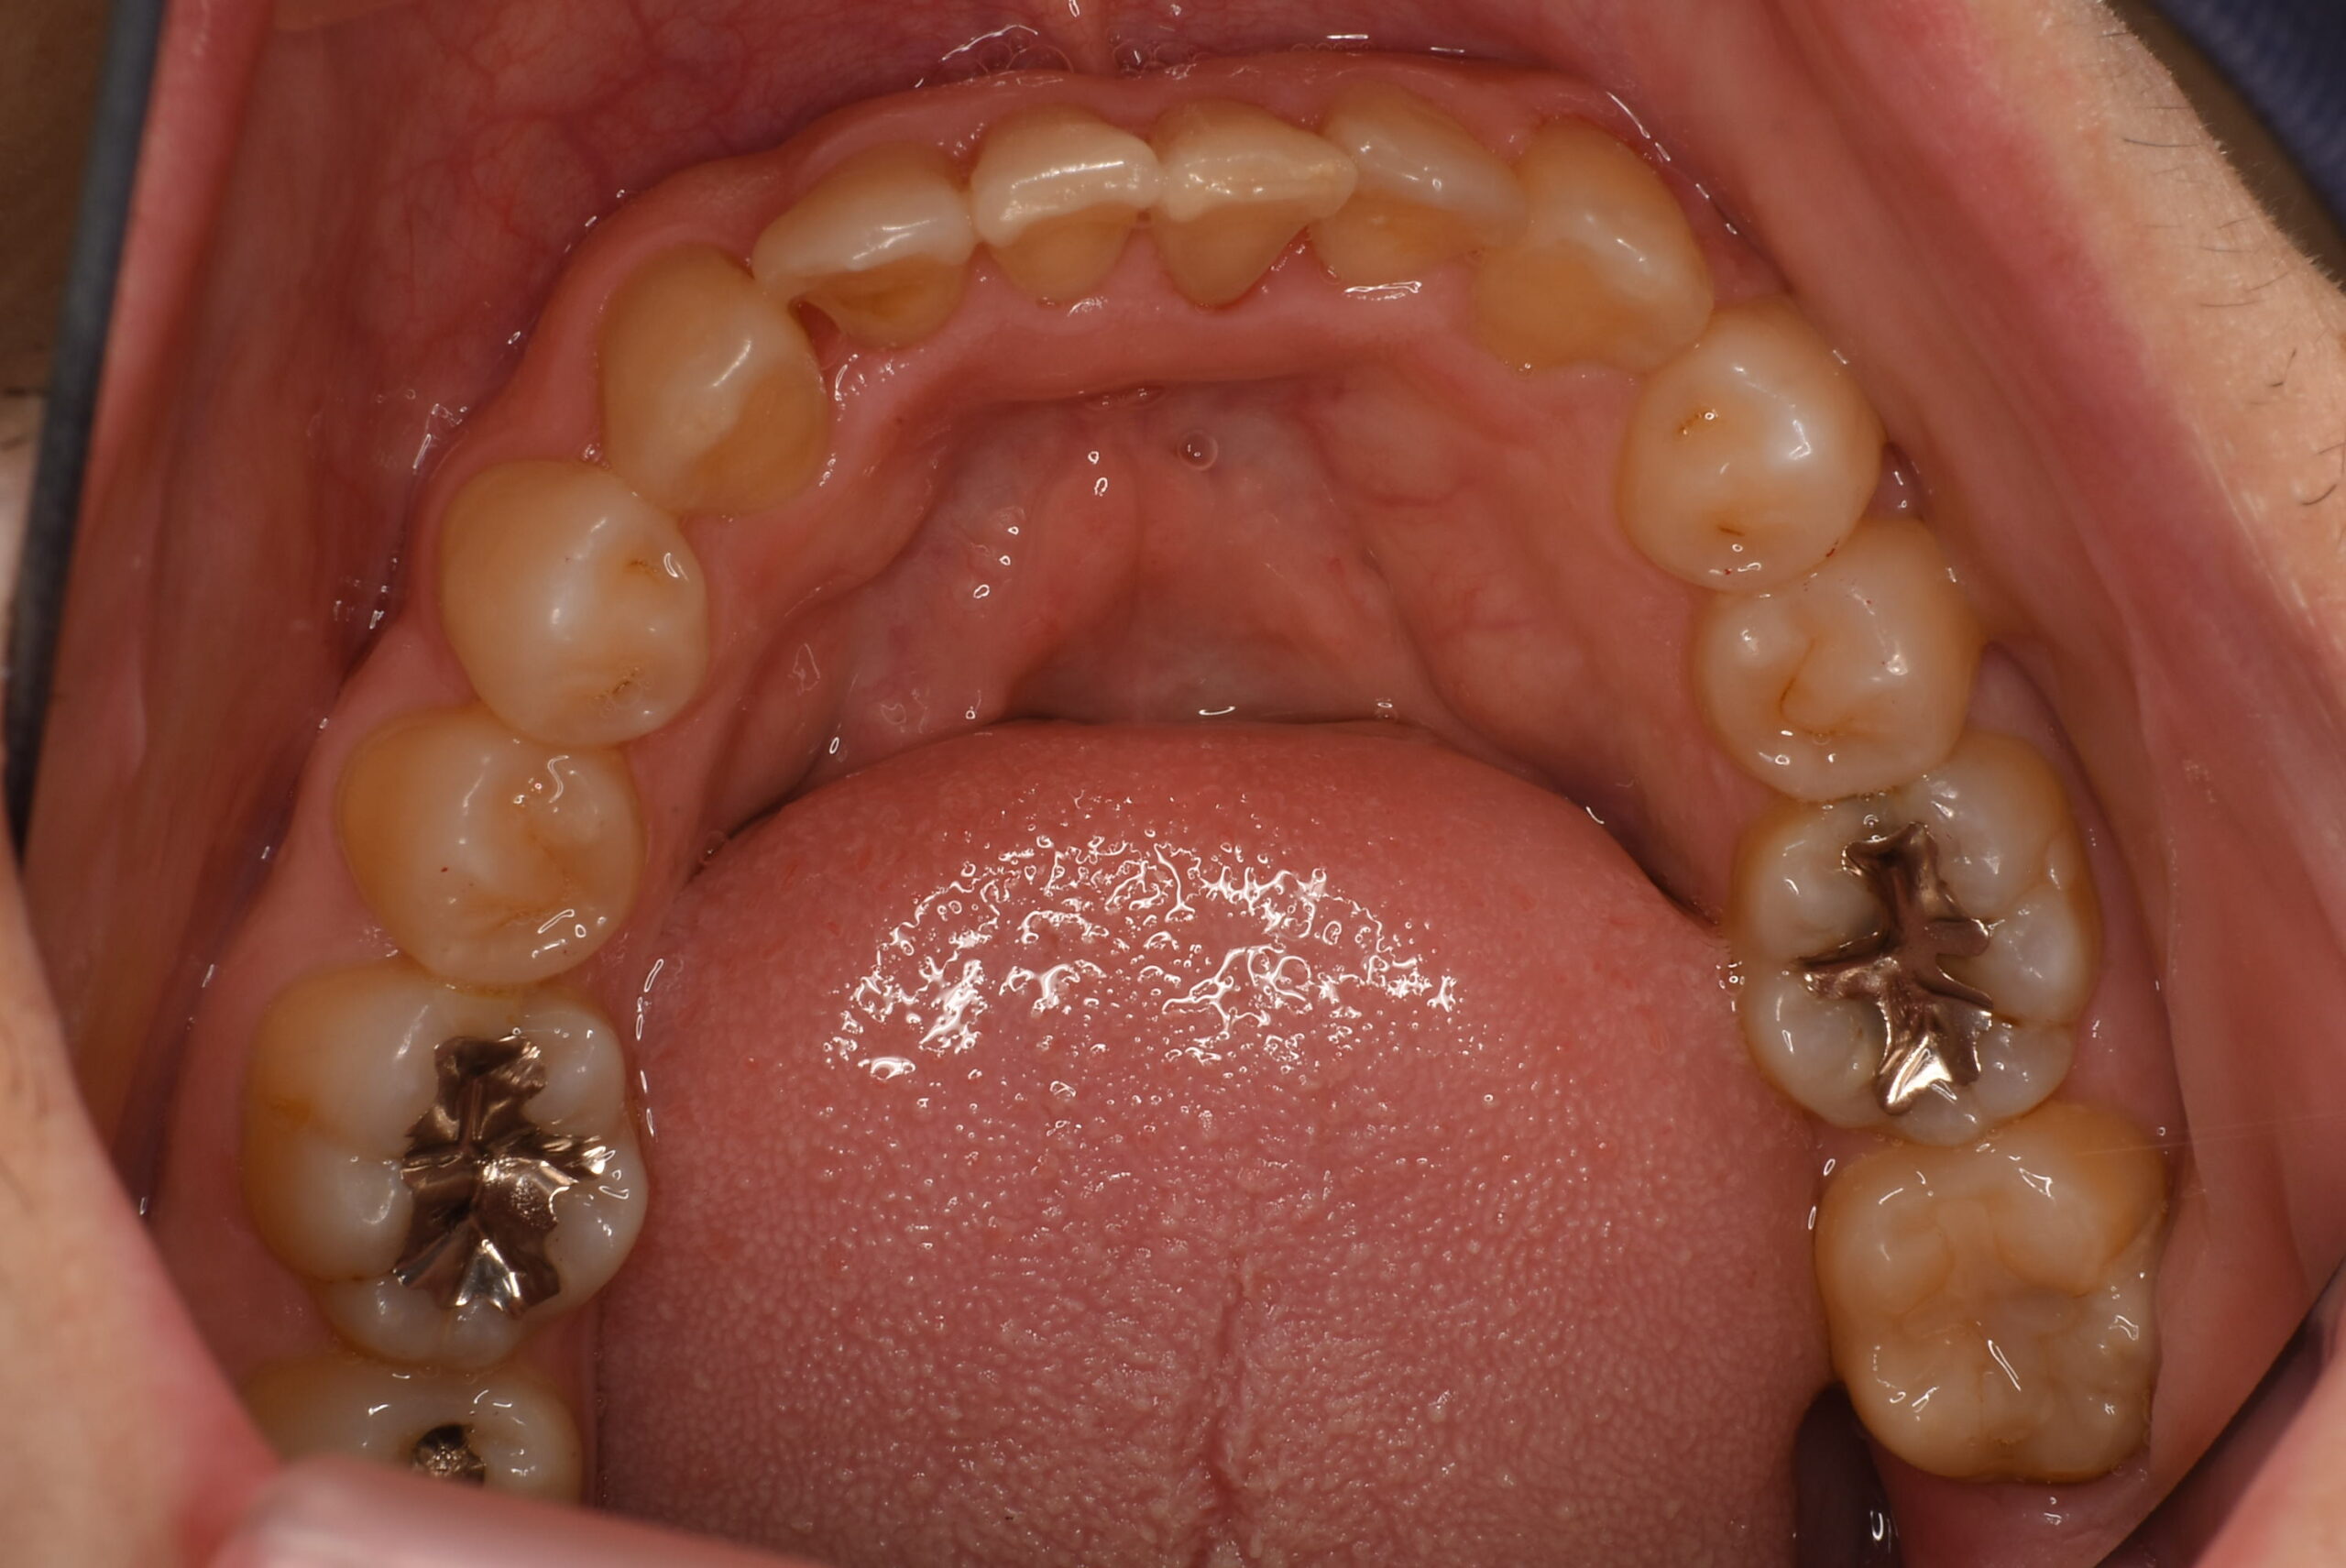

治療後_下顎咬合面

治療前_下顎咬合面